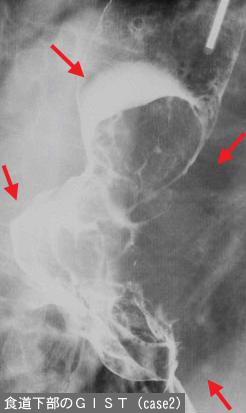

部位(臓器別)食道/下

検査方法X-P

腫瘍の肉眼分類1型(腫瘤型)/

病変の最大径(ミリ)30〜34